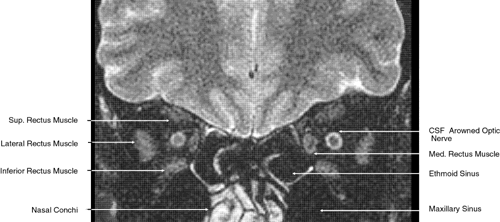

Fig. 30. A. Axial T1-weighted image at the level of floor of orbit and trigeminal nerve. B. Axial T1-weighted image at the level of oculomotor nerve.

Fig. 31. Axial T1-weighted image through the cerebral peduncle at the level of oculomotor nerve.

The globe is shown in Figure 12. The orbit and periorbital structures are shown in Figures 13 through 16, and the optic canal is shown in Figures 17 through 26. The cavernous sinus and optic chiasm are shown in Figures 27 and 28, and the posterior visual pathway and cranial nerves are shown in Figures 29 through 33.